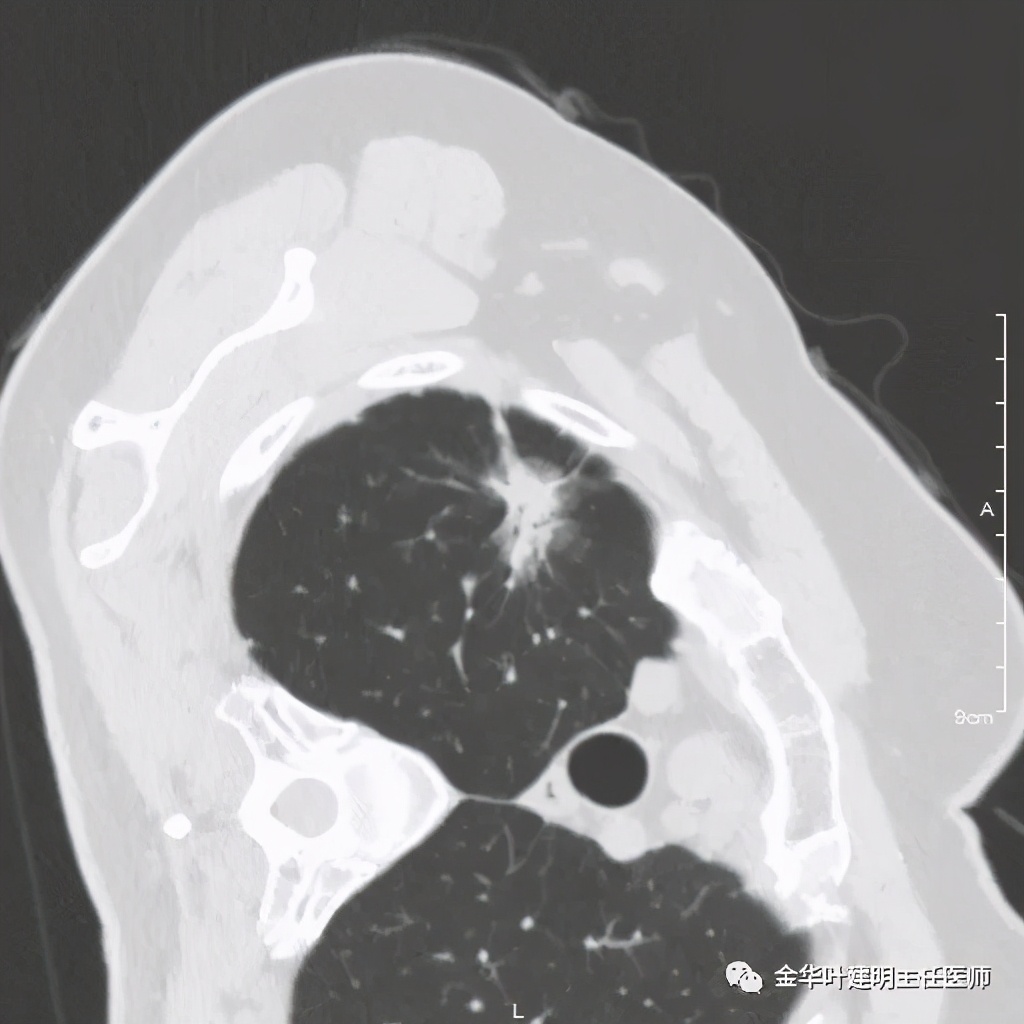

四、浸润性腺癌贴壁伴恶性度较高的实性成分:

影像特征:浸润性腺癌的贴壁生长型若伴有乳头、微乳头、实体型等成份时,更是典型的恶性的特征。此例是贴壁占60%,乳头成分占40%。我们来看其特点:桔色箭头示磨玻璃成分(代表贴壁生长部分),中央是实性成分(代表乳头生长部分),而且实性部分有收缩力(病灶向中间拉的趋势),密度高的部分又其内部密度不大均匀,毛刺也是长短不一。也就是说: 混合磨玻璃结节伴实性部分的收缩力 是其最显著的特点。实性部分若是实体型,也一般是类似表现。预后情况主要看实性成份的占比及亚型,因为贴壁成分是恶性度不高的,但若位微乳头或实体型,那便预后会差一些。也比腺泡型差。